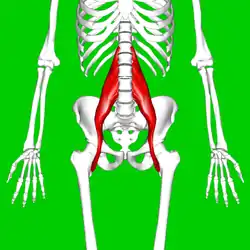

Position of psoas major (shown in red) | |

The psoas major (/ˈsoʊ.əs/ or /ˈsoʊ.æs/; from Ancient Greek: ψόᾱ, romanized: psóā, lit. 'muscles of the loins') is a long fusiform muscle located in the lateral lumbar region between the vertebral column and the brim of the lesser pelvis. It joins the iliacus muscle to form the iliopsoas. In animals, this muscle is equivalent to the tenderloin.

The psoas major is divided into a superficial and a deep part. The deep part originates from the transverse processes of lumbar vertebrae L1–L5. The superficial part originates from the lateral surfaces of the last thoracic vertebra, lumbar vertebrae L1–L4, and the neighboring intervertebral discs. The lumbar plexus lies between the two layers.[1]

Together, the iliacus muscle and the psoas major form the iliopsoas, which is surrounded by the iliac fascia. The iliopsoas runs across the iliopubic eminence through the muscular lacuna to its insertion on the lesser trochanter of the femur. The iliopectineal bursa separates the tendon of the iliopsoas muscle from the external surface of the hip-joint capsule at the level of the iliopubic eminence.[2] The iliac subtendinous bursa lies between the lesser trochanter and the attachment of the iliopsoas.[1]